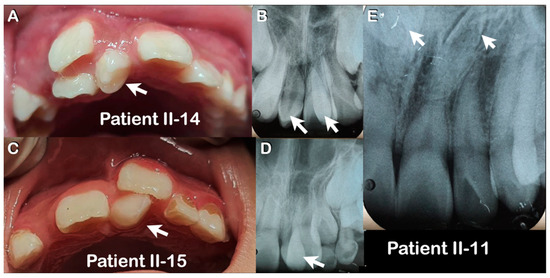

| Family 1 | II-14 | Hmong | Male | Double mesiodentes | Normal | Erupted | c.1807G>A; p.Glu603Lys; rs141113890 |

| II-15 | Hmong | Female | Single mesiodens | Normal | Erupted | ||

| II-11 | Hmong | Male | Double mesiodentes | Inverted | Unerupted | ||